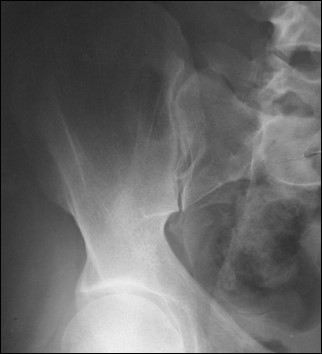

What are Judet views used for?

Evaluation of acetabular fractures.

<p>Evaluation of acetabular fractures.</p>

What is the patient position for an external oblique Judet view?

Affected side down 45°.

<p>Affected side down 45°.</p>